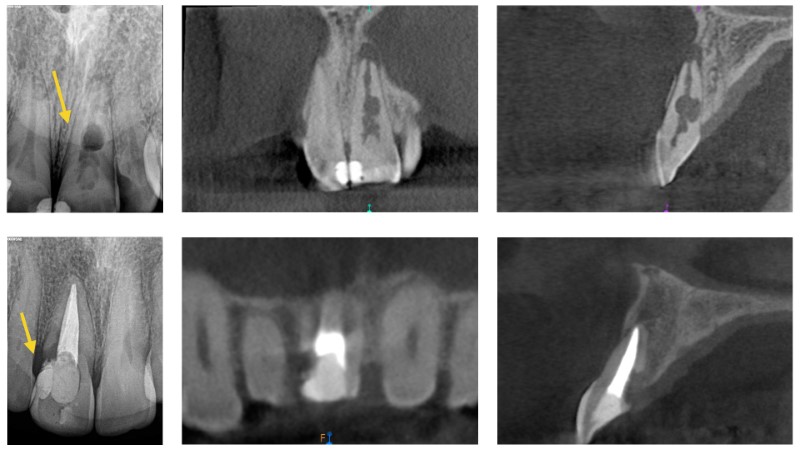

Radiografías Intra/ExtraOrales